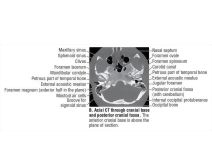

Axial CT Through Cranial Base and Posterior Cranial Fossa